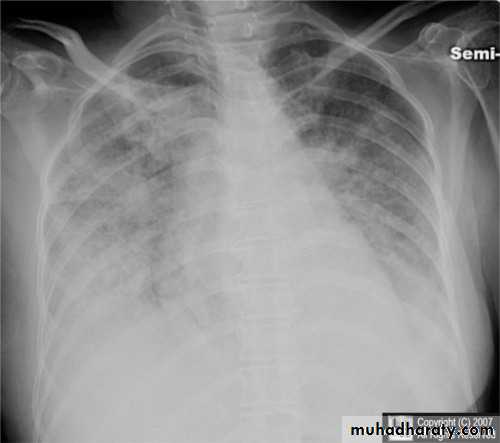

Miliary TB

65.Miliary TB

66. miliary TB